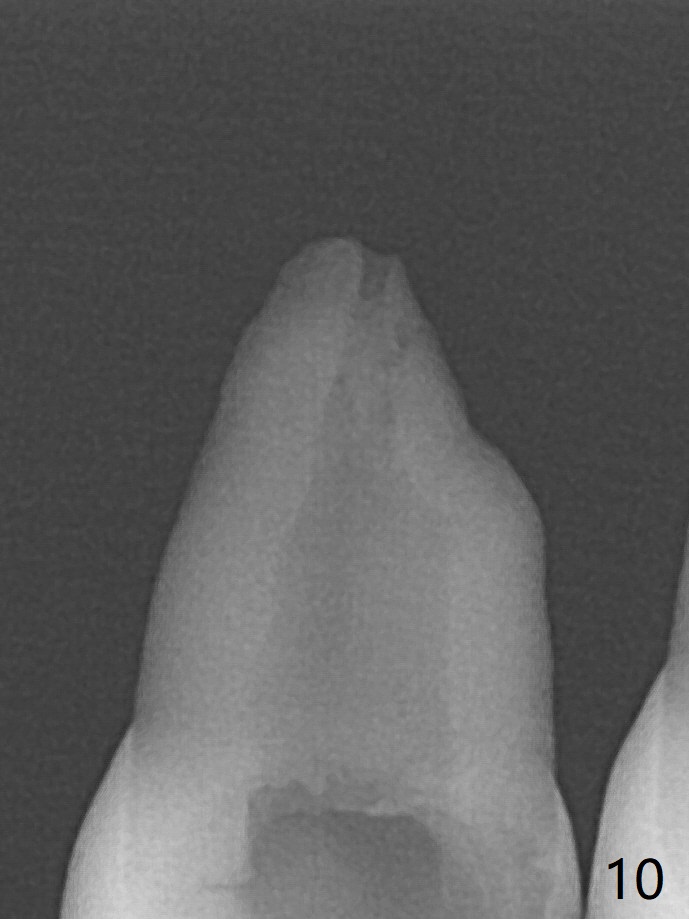

A 14-year-old woman with crowding returns to clinic for extraction of the 1st bicuspids. Orthodontic treatment has started partially. Because of severe caries at UR5 (Fig.1 *), BWs and PA are taken, which reveal DO incipient caries at UL, LL5 (Fig.2) and large PARL at UR5 (Fig.3 *). Upon receiving a revised treatment plan, four of 2nd bicuspids are extracted. The large PARL is confirmed intraop. Examination of the extracted teeth shows mesial caries at UL5, which is not detected by X-ray (Fig.4 <). By comparison, DL caries of UL5 is more severe (Fig.5). Check the neighboring teeth for caries when the patient returns for recall. The pulpal exposure of UR5 is large (Fig.6). So is the pulpal chamber (Fig.7). The large canal (Fig.7) in fact consists of 2 ones (Fig.11 red arrows) with a separation in between (*). The DL caries at LL5 is at the stage of decalcification (Fig.8), not visible in X-ray (Fig.12, as compared to Fig.7 >).